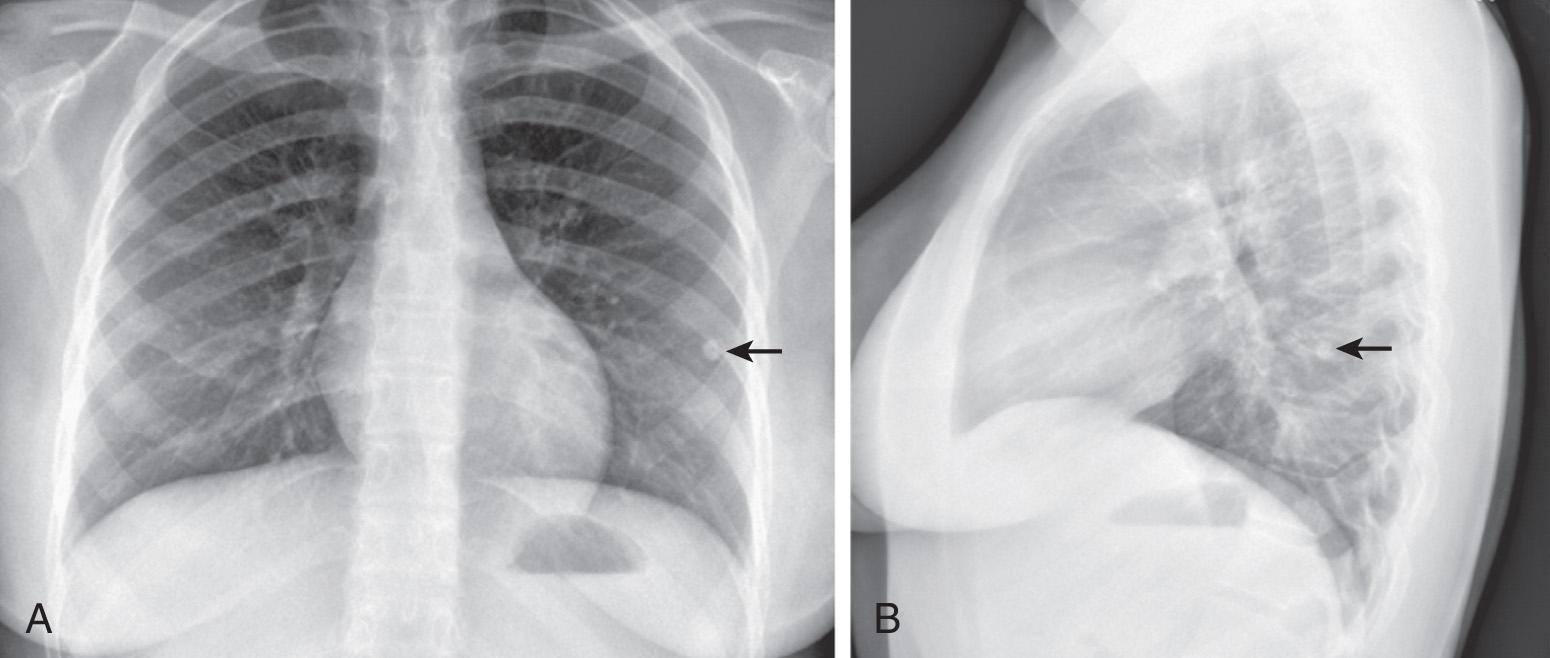

Fig. 242.6, Posteroanterior ( A ) and lateral ( B ) chest radiograph images of an adolescent showing a 7 mm calcified granuloma in the left lower lobe (arrows) .

The primary complex (or Ghon complex) of tuberculosis includes local infection at the portal of entry and the regional lymph nodes that drain the area. The lung is the portal of entry in >98% of cases. The tubercle bacilli multiply initially within alveoli and alveolar ducts. Most of the bacilli are killed, but some survive within nonactivated macrophages, which carry them through lymphatic vessels to the regional lymph nodes. When the primary infection is in the lung, the hilar lymph nodes usually are involved, although an upper lobe focus can drain into paratracheal nodes. The tissue reaction in the lung parenchyma and lymph nodes intensifies over the next 2-12 wk as the organisms grow in number and tissue hypersensitivity develops. The parenchymal portion of the primary complex often heals completely by fibrosis or calcification after undergoing caseous necrosis and encapsulation ( Fig. 242.6 ). Occasionally, this portion continues to enlarge, resulting in focal pneumonitis and pleuritis. If caseation is intense, the center of the lesion liquefies and empties into the associated bronchus, leaving a residual cavity.